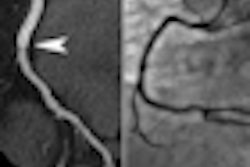

When using CT to assess graft patency after coronary artery bypass graft (CABG) surgery, employing a variable-pitch technique speeds scanning and reduces contrast dose by a third, Japanese researchers said in a presentation earlier this month at the RSNA meeting in Chicago.

"Graft patency could be accurately assessed in all patients," Ishihara said.

With vHP scanning, the volume of contrast media injected could be reduced by approximately 33%, while maintaining CT values not significantly different from those in non-vHP scanning, Ishihara said.